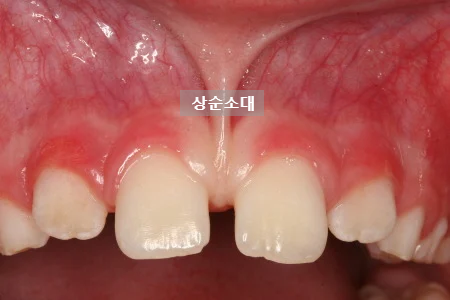

윗입술과 잇몸을 연결하는 작은 조직을 상순소대라고 합니다.

이 조직이 비정상적으로 두껍거나 길거나, 앞니 사이까지 깊게 내려와 있는 경우, 앞니 사이를 벌어지게 만드는 힘으로 작용할 수 있습니다.

상순소대가 정중이개의 주요 원인인 경우, 교정치료와 함께 상순소대 절제술을 병행하여 치료 후 공간이 다시 벌어지는 것을 예방할 수 있습니다.

따라서 일반적으로는 치아이동으로 앞니 사이 공간을 먼저 닫은 후, 재발 방지를 위해 순소대 절제술을 시행하는 것이 바람직합니다.

이후 교정적으로 위 앞니 사이의 공간을 닫아 정중이개를 해소하고, 마지막으로 재발 방지를 위한 상순소대 절제술을 시행했습니다.